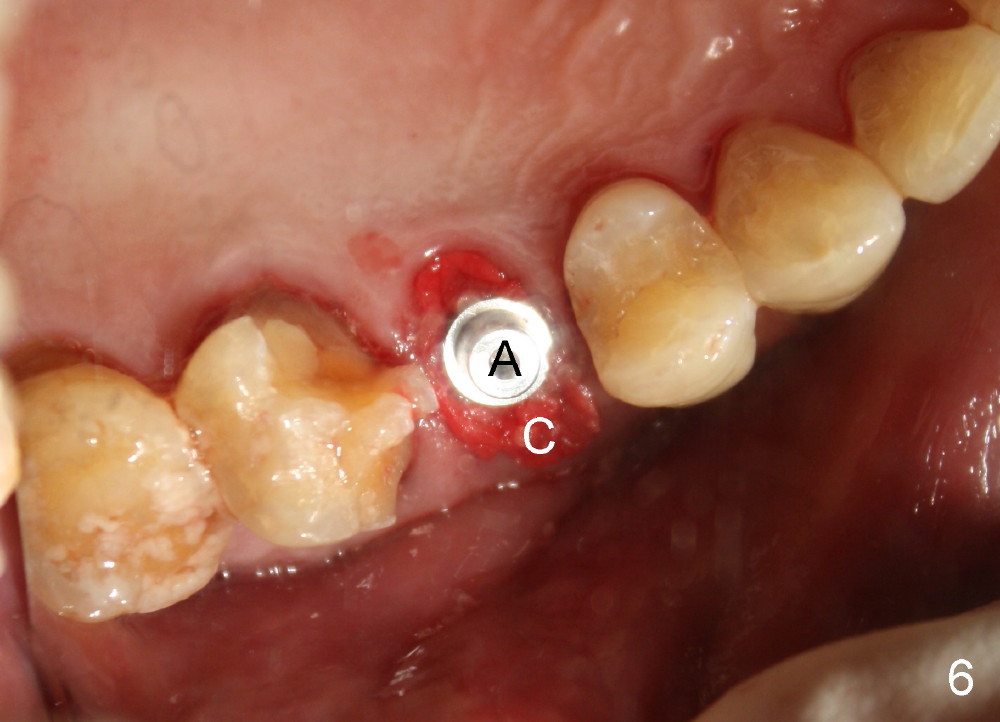

A 72-year-old man is a bruxer with #3 cusp fracture with chronic periapical radiolucency (Fig.1 *) and #4 acute crack.  It appears reasonable to take care of emergency (#4 extraction and immediate implant (Fig.3-7: 4.5x20 mm, 45 Ncm)) followed by root canal therapy or extraction for #3.  Eight (Fig.8) and 14 (Fig.9-11) days postop, the patient is doing fine and the wound heals normally.  But he does not agree any treatment for #3, since it is asymptomatic in spite of a fistula associated with the tooth (Fig.8,9 >).  Three months postop, the patient is still asymptomatic and is ready for #4 restoration since the tooth #28 cracks.  Follow-up PA shows the persistent distal gap (Fig.12 >, as compared to Fig.4), accompanied with crestal bone resorption (*).  Clinically the implant has mild mobility and light tenderness. The patient still refuses #3 treatment. It appears that the implant has failed to osteointegrate.  In brief, do not place an immediate implant next to active infection.